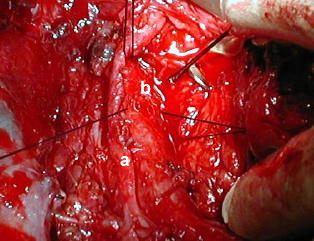

Procedimiento reparador

• Una hilera de puntos simples, con material de lenta absorción, calibre 4-0, equidistantes 1,5 mm, en la semicircunferencia posterior traqueal y en ambos cabos se van refiriendo y su posterior anudación externa (nudo por fuera de la traquea) es realizada, este procedimiento aproxima el cabo distal intubado al cabo superior convirtiéndose en una maniobra de extrema delicadeza que obliga a retirar el tubo corrugado y avanzar el tubo orotraqueal en sentido distal y este es guiado por el cirujano dentro del cabo distal para evitar desgarros.

• El tubo de ventilación de la maquina anestésica ahora es conectado al tubo orotraqueal.

• Una nueva hilera de puntos de iguales caracteristicas es efectuada en la semicircunferencia anterior de los cabos traqueales, y como en la cara posterior, se van anudando uno a uno quedando el nudo del lado externo de la traquea.

• Terminado de anudar, la línea de sutura fuerte y hermética ascendió en el mediastino, El punto de referencia anterior de calibre 3-0, mas grueso y extramucoso fué anudado a manera de refuerzo de la anastomosis.